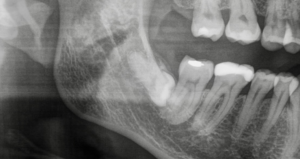

Mikor kell eltávolítani a bölcsességfogat?

A bölcsességfogak (harmadik molárisok) eltávolítása akkor válhat szükségessé, amikor problémákat okoznak vagy jelentős kockázatot jelentenek. Ilyen esetek például:

- A csontban részben vagy egészben bennrekedt (impaktált) fogak

- Fogtorlódás, fogromlás veszélye áll fenn

- Szuvasodás, fertőzés, ínybetegség

- Bölcsességfog körüli ciszta kialakulása